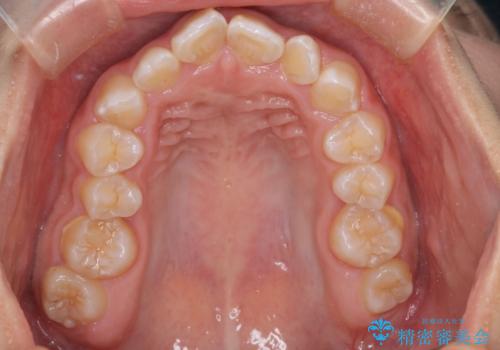

マウスピース矯正で前歯のガタツキを改善! ワイヤー矯正併用でかみ合わせもしっかり治します

- 前歯のガタツキが気になると来院されました。

マウスピース矯正治療を選択しました。

前歯のガタツキを改善する治療法として、マウスピース矯正が適していることが多いです。

マウスピース矯正は、金属製のブラケットやワイヤーを使用せずに、透明なマウスピースを装着して歯を移動させる方法です。そのため、目立たず、痛みも少ないです。